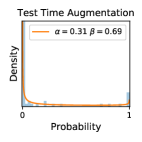

To model how different classifiers will respond to a given input , we assume that the prediction from classifier is sampled from a beta distribution that is characterized by two parameters by and . We further assume that is fixed to the same constant value for all ’s. Under this assumption, each input can be described by ( can be calculated since is fixed), easing further analysis. The Severity Level (SL) of the case represented by image can be characterized by the parameter . The larger the value of , the more severe the case of is. When and are close, the case is ambiguous as the distribution shifts towards being symmetric (i.e. signifying much disagreement among classifiers) rather than being one-sided (i.e. consensus among classifiers that is negative or positive). We provide a set of examples in Figure 2 and also Figure S.8 in the supplementary materials showing how the beta distribution can be used to capture diverse predictions given by an ensemble learner.

We conducted a case study on diagnosing diabetic retinopathy with ensembles of DL models. For benchmarking the performance of our ensemble-based solutions under the scheme described in Sec.3.3, we used two popular collections of diabetic retinopathy image data, the Kaggle Diabetic Retinopathy dataset [22] (hereafter referred to as “Kaggle-DR”) and the Messidor-2 dataset [23], each respectively consisting of and high resolution images. Diabetic retinopathy is graded into five SLs, as displayed in Figure 2. Following the problem setup used in previous papers [24], we trained models to distinguish the referable (SL2-4) cases from the non-referable ones (SL0 & SL1) (see Section B.1 for more detailed descriptions). We also tested our trained ensemble models on two o.o.d. image datasets (ImageNet [25] and CIFAR-10 [26]) to examine their capabilities of identifying o.o.d. inputs (see Section B in the supplementary materials).

In contrast, the MC-dropout method showed the worst overall performance among the three, as it can be seen from the high ratios of SL0 examples among the uncertain negatives in Figure 4. The histograms in Figure 2 provides another perspective to look into the phenomenon, where a decent proportion of MC-dropout model’s predictions on SL0 inputs entailed low confidence (far from 0 or 1), which from another angle explained why MC-dropout was less specific in terms of lower FNP; many no-DR inputs (i.e. SL0) were erroneously assigned high uncertainty by MC-dropout models.

It is still an open question why the evaluated MC-dropout networks signaled relatively high uncertainty on SL0 & SL3 & SL4 data that are less likely to be ambiguous. We conjecture that much of the “uncertainty” indicated by disagreement among test-time dropout samples actually reflects the stochastic nature of dropout networks rather than the real decision uncertainty associated with the data. It is worth noting that the MC-dropout model we evaluated was not weak per se; they all achieved above Area Under Curve (AUC) scores on test sets. The weakness of individual test-time samples (which explains their low-confidence predictions on SL0 & SL3 & SL4) might have been hidden when they are aggregated into an ensemble—a well-known advantage of ensemble learning. Our results suggested that the uncertainty information given by implicit ensemble methods such as MC-dropout and TTA might not be as reliable as that from explicit ensemble approaches (e.g., stacking ensembles). Similar findings on MC-dropout can be found in some previous papers [1].